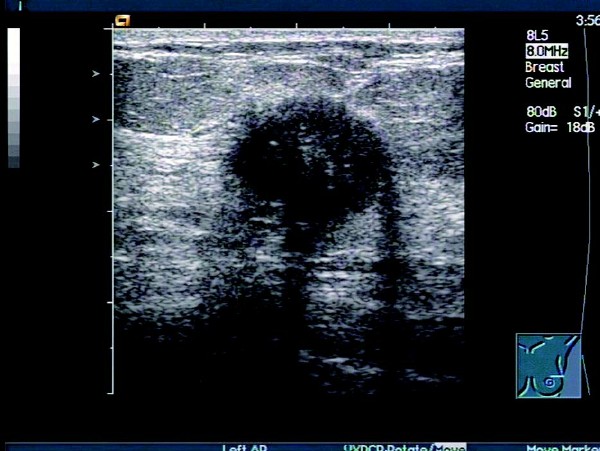

患者,女,46岁。查体时发现右乳腺一肿物,活动度差,质硬。超声检查报告显示:右侧乳腺外上下象限乳腺边缘可见一大小约1.5 cm×1.2cm的偏低回声团,边界不清晰,形态不规则,包膜不明显。内部回声不均匀,可见少量沙砾样强回声点,纵横比>1,偏低回声团后方衰减明显。CDFI:其内可见短管样血流信息,动脉可见高速,高阻血流信息。

超声提示:右侧乳腺实质性肿块伴钙化,考虑乳腺癌